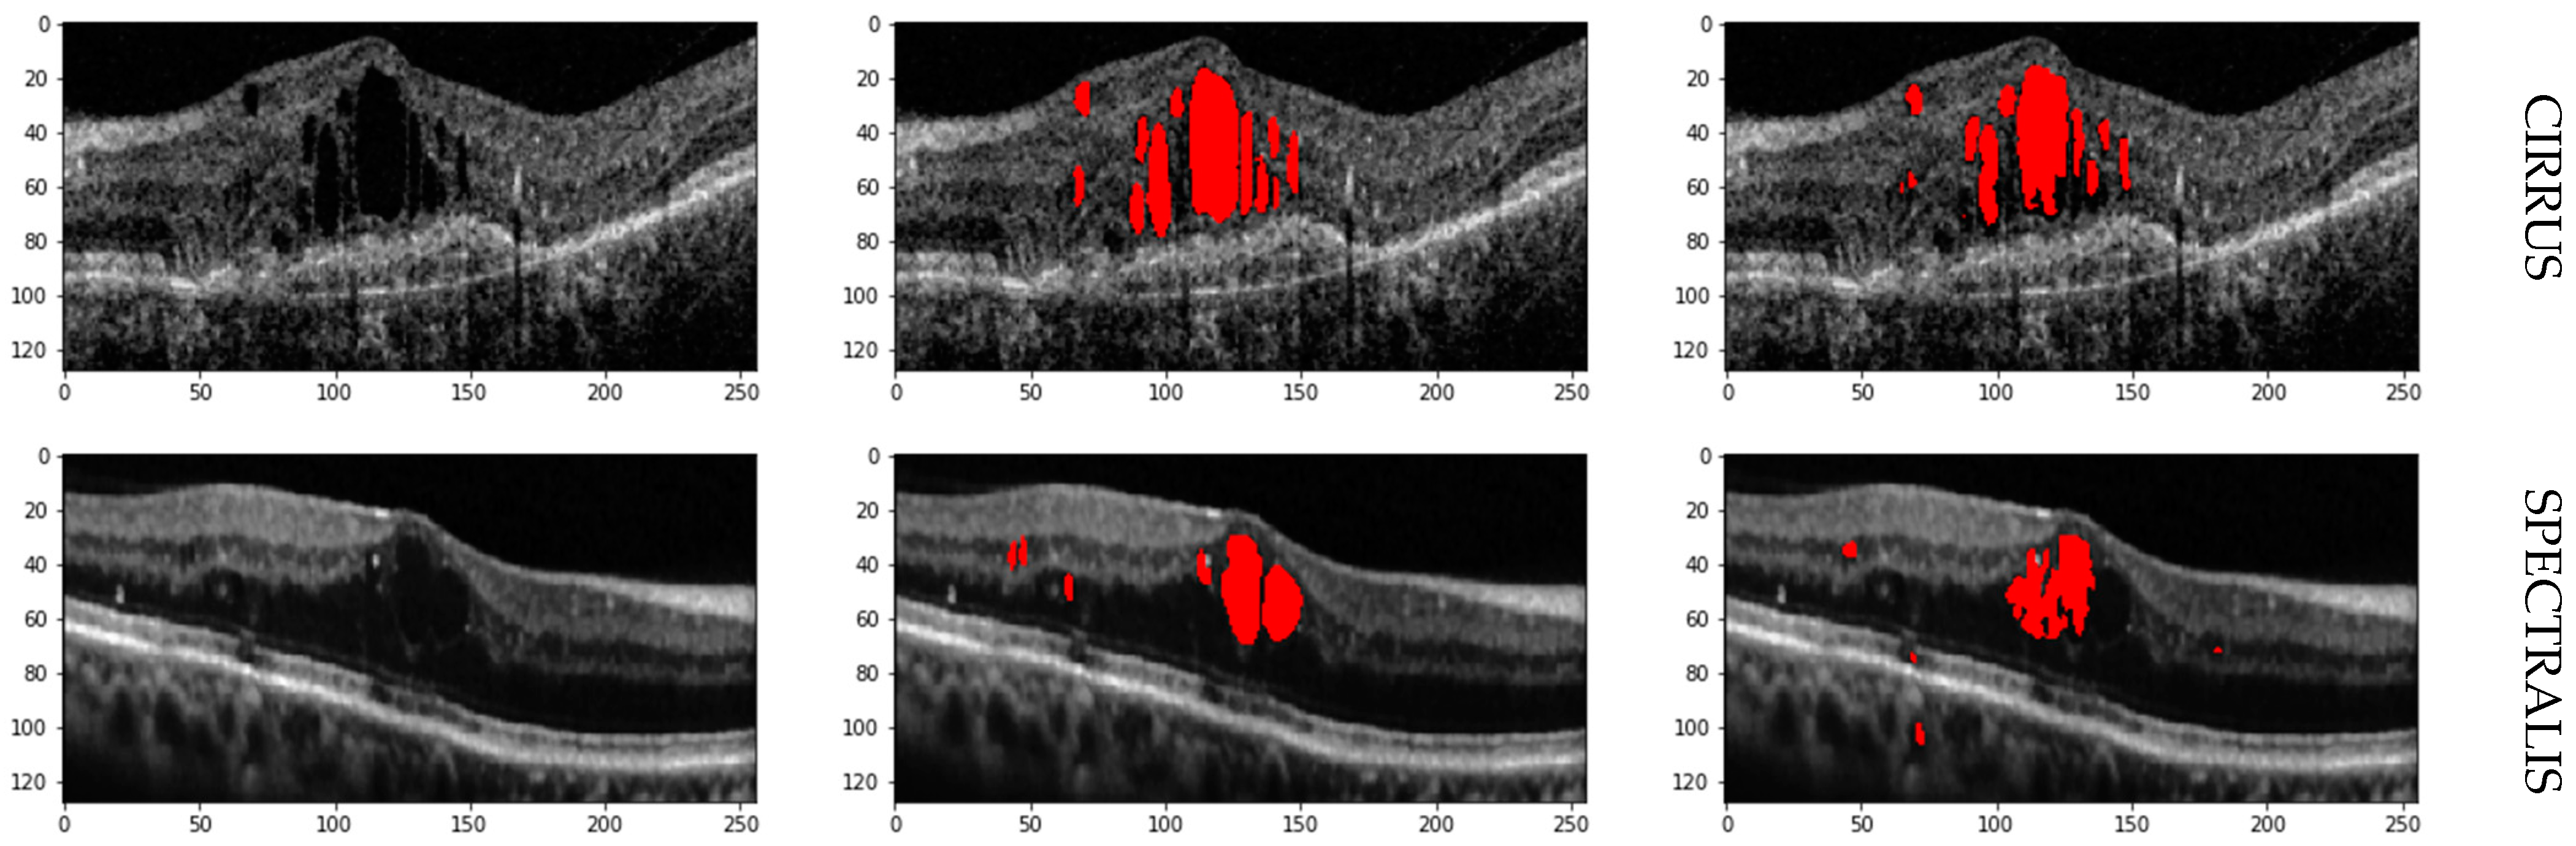

In this Section, we’ll discuss our segmentation results on various datasets. Additionally, we will compare our hybrid U-Net with existing methods to comprehensively understand its performance. In all the test images, red indicates IRF, blue indicates PED, and green indicates SRF5.1. Performance Metrices

5.2. Results on RETOUCH Dataset

The provided Table 1 details the performance metrics—Precision (Pr), Recall (Re), and F1 Score (F1)—for segmenting intraretinal fluid (IRF), subretinal fluid (SRF), and pigment epithelial detachment (PED) using OCT scans from three vendors: Cirrus, Spectralis, and Topcon. The metrics for each fluid type and the overall averages across all vendors are presented.

For Cirrus scans, the segmentation network demonstrates balanced performance with an F1 Score of 0.82 for IRF and exceptional performance for SRF and PED, achieving F1 Scores of 0.93 and 0.94, respectively. This results in high average metrics, with Precision, Recall, and F1 Score of 0.90, indicating robust and reliable segmentation. Spectralis scans also show balanced performance for IRF with an F1 Score of 0.81 and excellent performance for SRF, achieving the highest F1 Score of 0.95 among all metrics. The PED segmentation is consistent with an F1 Score of 0.91, leading to overall averages of 0.90 for Precision, 0.88 for Recall, and 0.89 for F1 Score, suggesting reliable segmentation with slight variation in recall. Topcon scans exhibit slightly lower performance compared to Cirrus and Spectralis. The IRF segmentation has a lower Precision of 0.69, resulting in an F1 Score of 0.74. SRF and PED segmentation show moderate performance with F1 Scores of 0.89 and 0.92, respectively.

The overall averages for Topcon are 0.84 for Precision, 0.86 for Recall, and 0.85 for F1 Score, indicating slightly lower but still effective performance. The segmentation network achieves a well-balanced and robust performance across different vendors and fluid types, with an overall average Precision, Recall, and F1 Score of 0.88.

The high average F1 Scores and balanced Precision and Recall metrics confirm the network’s robustness in accurately identifying and segmenting IRF, SRF, and PED in OCT images. Cirrus and Spectralis devices show the highest performance, while Topcon demonstrates slightly lower performance yet still effective segmentation capabilities. Retinal fluid Segmentation using the proposed model on the RETOUCH dataset is given in Figure 5. Figure 6 shows the Receiver Operating Characteristics (ROC) of the retouch dataset with various vendors with corresponding Areas under Curve (AUC).

Figure 5. Retinal fluid Segmentation using the proposed model on the RETOUCH.